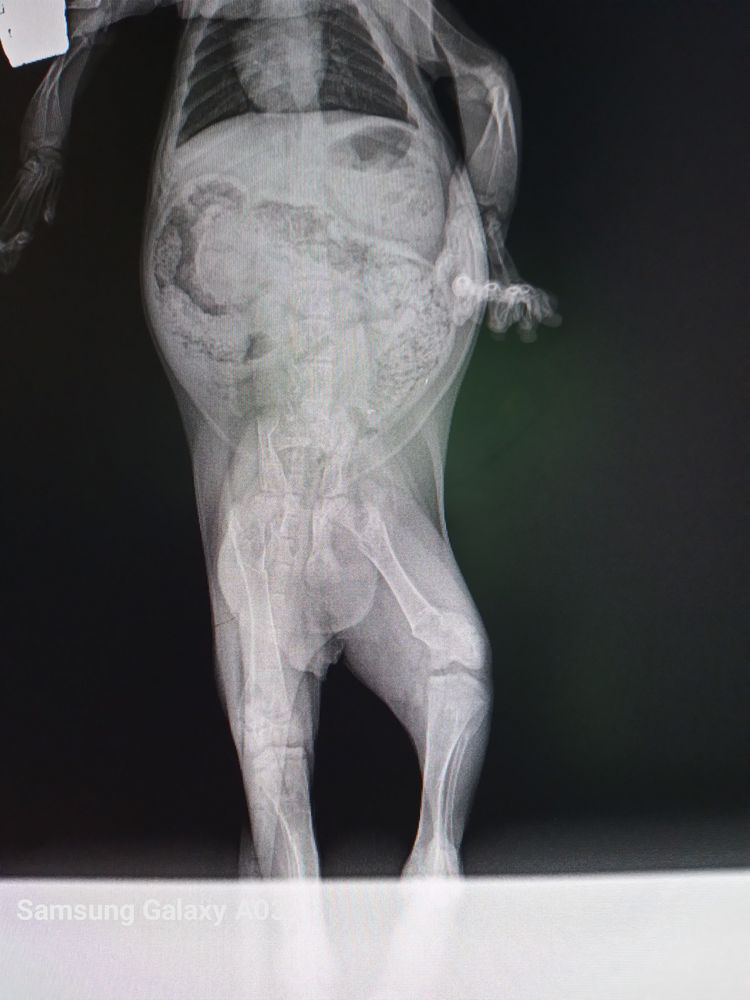

Котенок 4 месяца, застарелые, неправильно сросшиеся перелому задних лапок

Вареник, есть рентген снимок. Позвоночник с середины и до тазовых костей как кривой забор, перелом колена, шейка бедра, как сказал доктор, как будто оторвана и уже все заросло хрящевыми мозолями. Мы бы и не знали ничего не начни он хромать, думали, может кошка придавила, или мы нечаянно на лапку наступили, он же маленький, постоянно под ногами крутится. Дискомфорт, конечно, есть, он хромает, ходьба ему дается очень тяжело. Есть так же видео как ходит Изображение

Вареник, и еще доктор сказал, что раньше это не доставляло ему беспокойства, пока он не начал активно расти. Он же ведь даже бегал и игрался как обычный кот. Существует ли такая вероятность, что когда он перестанет расти, прекратятся и его боли, и будет ему намного проще? Консультация хирурга ортопеда будет только 13 числа.